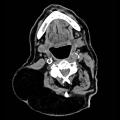

Lipome cervical

LIPOME

Image